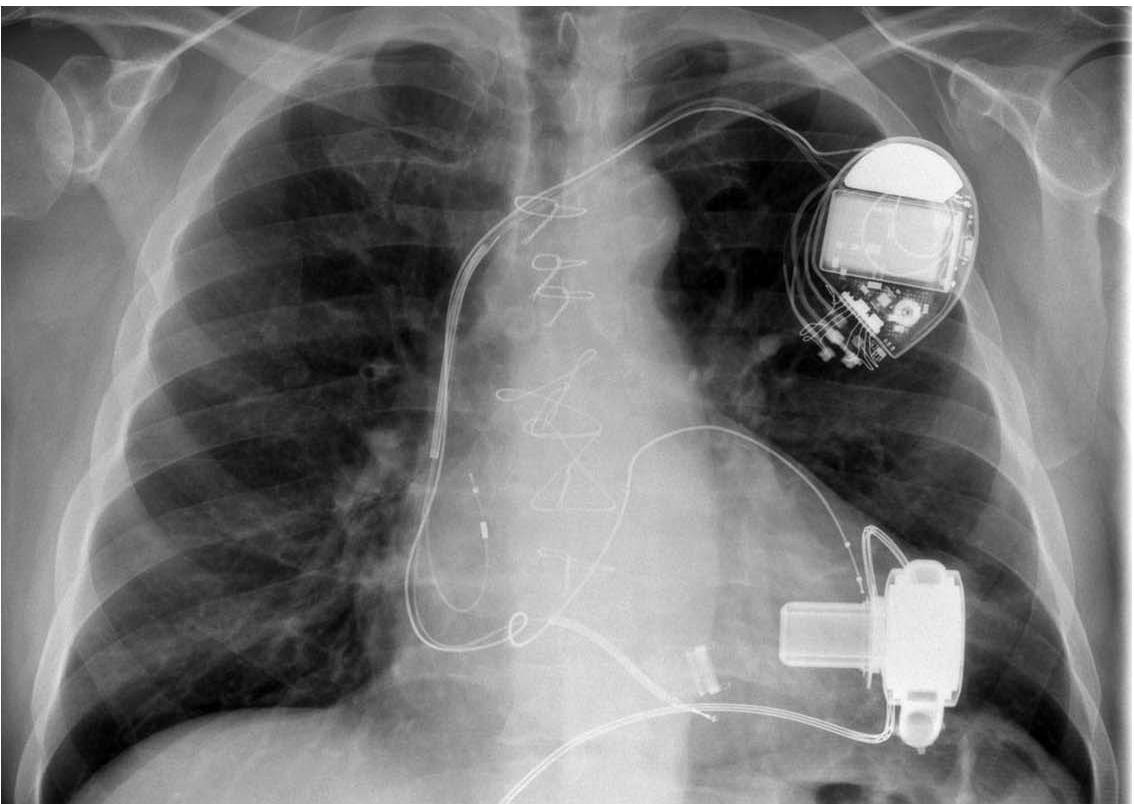

HeartWare HVAD

1. 离心泵,重145g,泵平均流量4.0-6.5L/min

2. 泵体很小,可直接放置心包内无需腹膜口袋